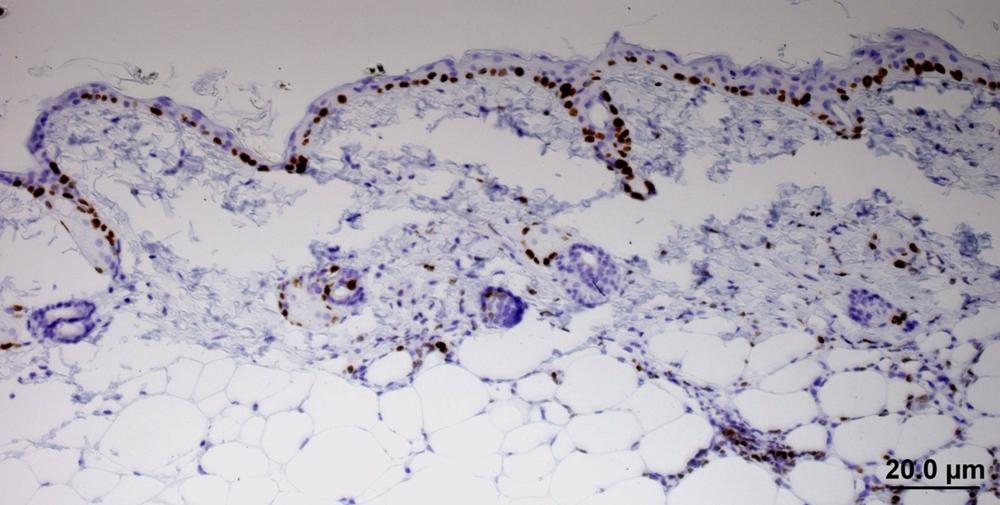

Los cánceres de los epitelios, que son los tejidos que recubren todas las superficies del organismo –la piel, pero también los revestimientos de los órganos–, están relacionados con un tipo de cambio que sufren las células epiteliales, llamado transición epitelio-mesénquima.

El trabajo, liderado por el investigador Cédric Blanpain, de la Universidad Libre de Bruselas, tiene como co-autores a los investigadores del CNIO Sara Rodríguez-Acebes y Juan Méndez, quienes observaron, en modelos de cáncer de piel en ratón, que la expresión de la proteína RHOJ es especialmente alta en las células resistentes a la quimioterapia.